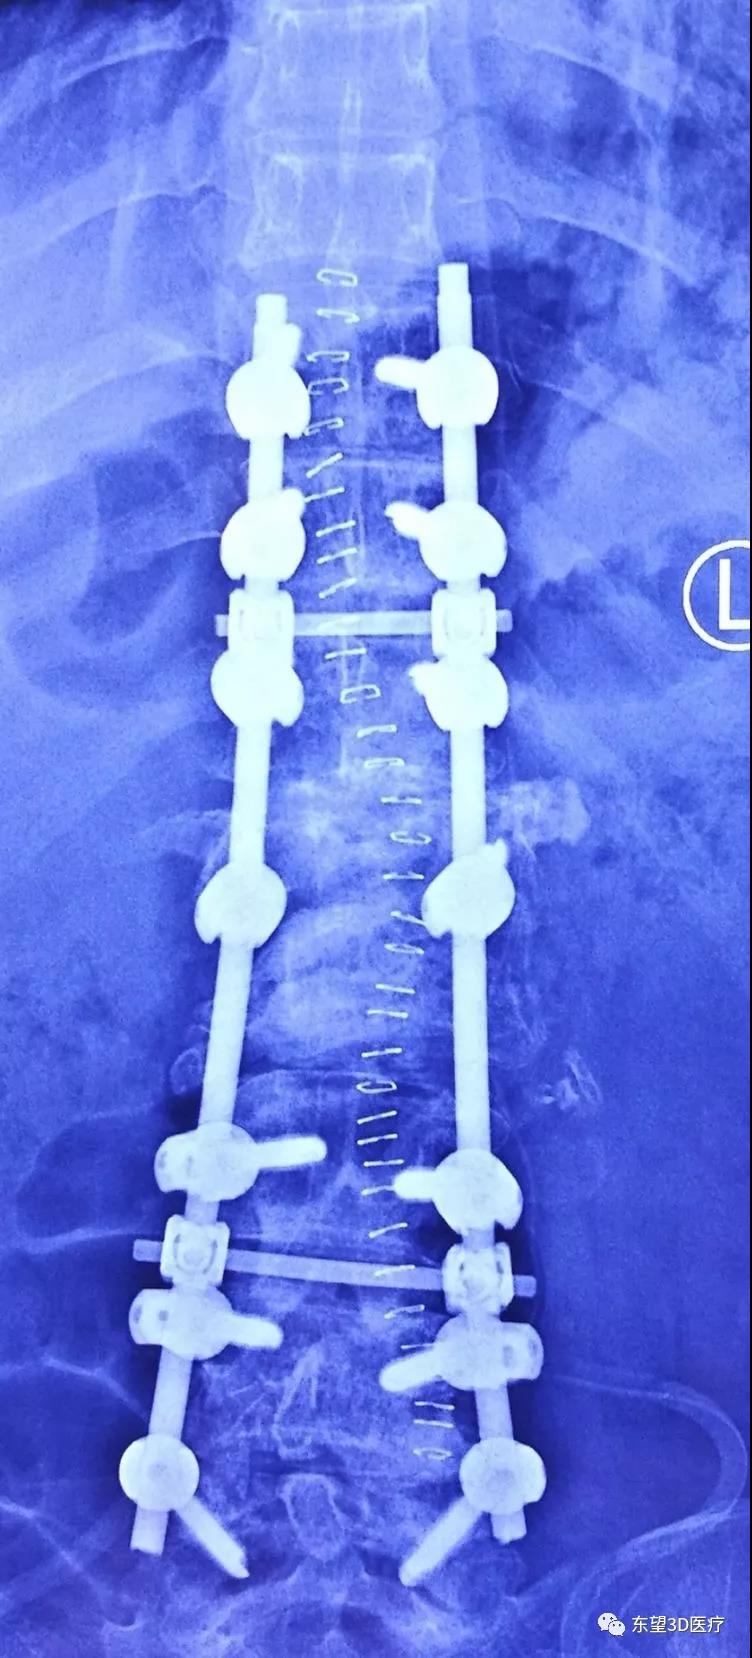

術后側位X片見后凸畸形消失,生理曲度恢復

\

術后正位X片見側凸及旋轉畸形消失,矯形理想。患者雙下肢疼痛麻木明顯好轉、肌力增加活動靈活,患者及家屬滿意。